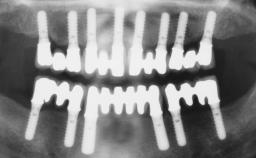

Conventional Loading of Six Implants in the Mandible and Final Restoration with a Full-Arch Metal-Ceramic FDP

# of Implants 6

Type of Implants One-Piece

Defining Characteristics Fully edentulous lower jaw to be rehabilitated with two or more implants

Modality > 4 implants, extending to mental nerve region

Bone Volume Horizontally and vertically sufficient